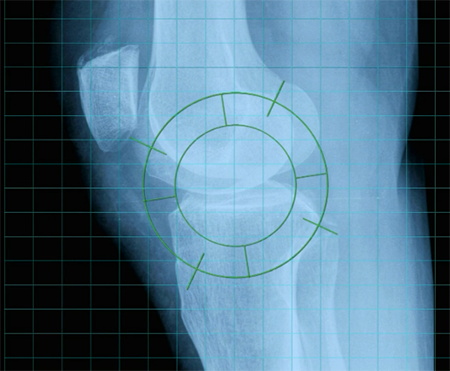

La Mineralometria Ossea Computerizzata (MOC) consente di valutare lo stato di mineralizzazione dell’osso, utilizzando ultrasuoni non dannosi e risulta ideale per lo screening e il controllo dell’osteoporosi.

La valutazione del rischio di frattura osteoporotica fornita da Achilles è molto precisa e la rende particolarmente utile per distinguere i soggetti non a rischio di frattura da quelli che necessitano di ulteriore valutazione.

L'esame è rapido e confortevole (una membrana riempita d'acqua calda abbraccia il calcagno), indolore, non invasivo e sicuro.